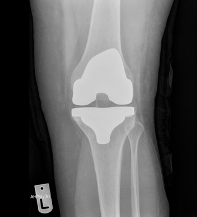

Images of Knee Replacement:

X-Ray of Knee Replacement 2